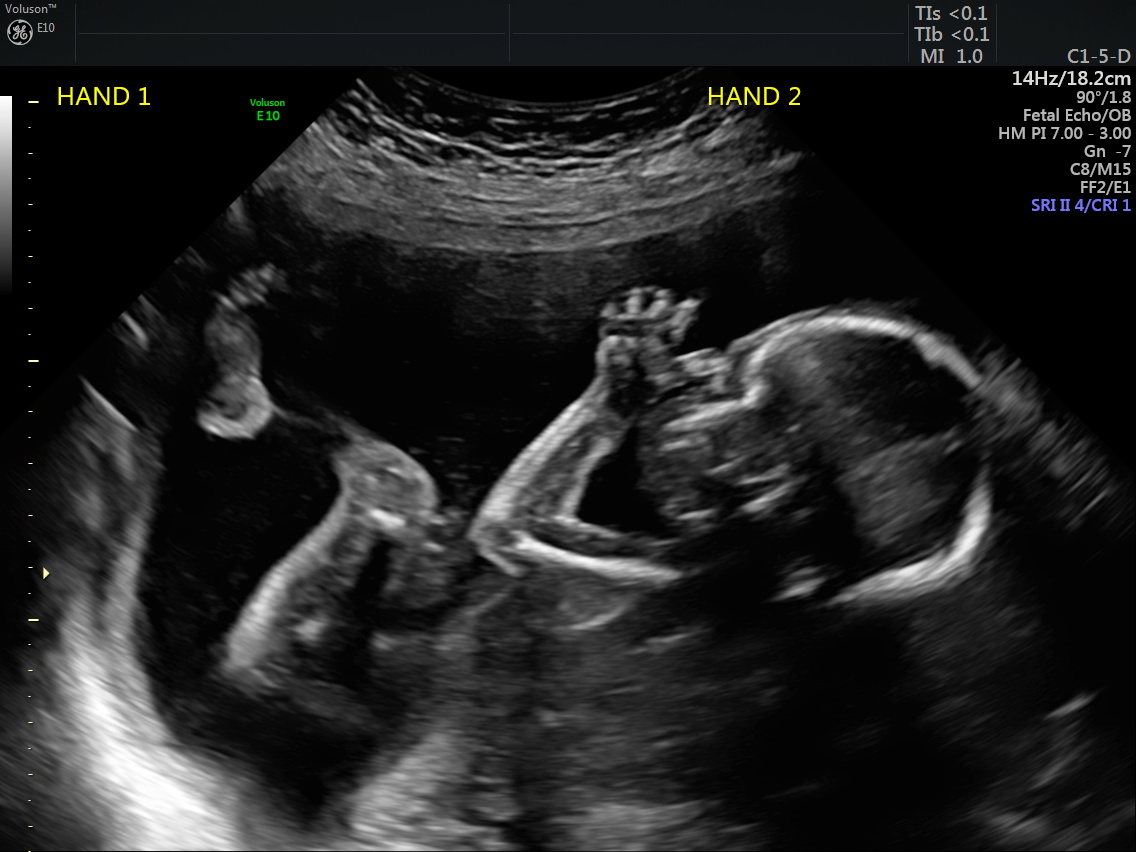

By and large, my pregnancy wasn’t too bad. I lucked out and had no nausea and very little discomfort. At 20 weeks, Brian and I went to the anatomy ultrasound and learned we were going to have a BOY. Our little boy has four boy cousins on my side, as well as quite a few boy distant cousins. (He’s the first in his generation on Brian’s side.)